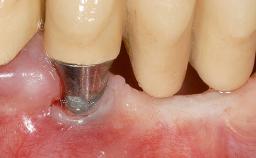

This case demonstrates that a connective-tissue graft in combination with a coronally positioned graft is an effective method of treating cases with peri-implant mucositis and an abutment-level sinus abscess. A 42-year-old man presented with a swelling adjacent to an implant crown at site 21. The swelling had been present for approximately three weeks and was constrained to the buccal and palatal gingival aspects of the implant. A discharge was noted on finger pressure, with localized gingival recession present on the mid- and distolabial aspects of the crown.

Type of Implants Two-Piece

Attachment Two-Piece